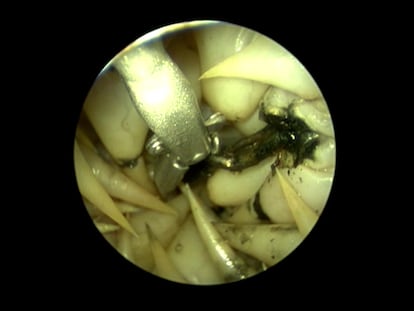

Impactantes imágenes de la intervención a este animal, que llevaba cerca de un mes atrapado en el puerto de Torrevieja